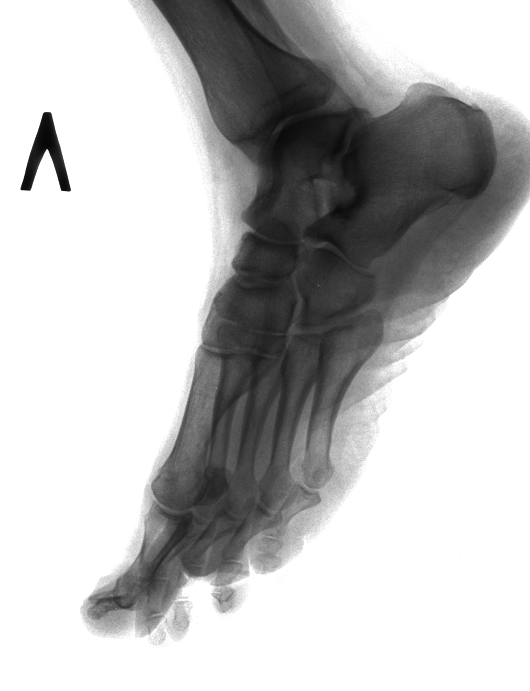

Интересный набор в одном суставе. Особое внимание привлекла физарная зона. Поделитесь мнениями, с какой нозологией/патологией можно связать? Левый сустав для сравнения в одной проекции.

Тип: Клиническое наблюдение

Область: Скелетно-мышечная система

Модальность: Rg

Дата: 23.11.2017 - 21:05